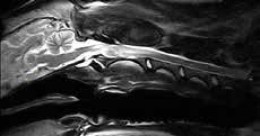

Vet-MR Grande дозволяє отримувати зображення високої якості, навіть у порівнянні з високопольними МРТ 1,5 тесла.

vet-mr-grande-3